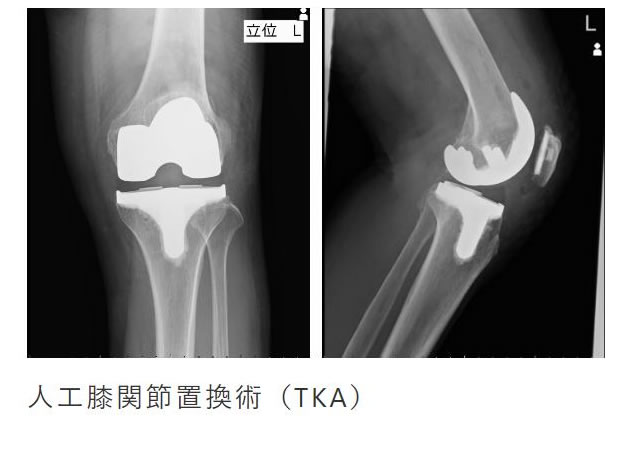

関節疾患

膝や股関節などの変形による疼痛や靭帯損傷に対して治療を行います。

変形の程度、疼痛が強い場合は人工関節置換術にて痛みの緩和を図ります。

当院では外来リハビリがありますので、関節の変形に対する予防的筋力トレーニングから、術後の回復トレーニングまで行えます。